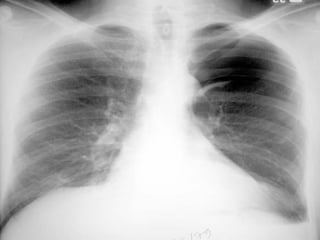

Pulmonary function tests  are weakly sensitive measures of the presence or size of pneumothorax and are not recommended   . Arterial blood gas measurements  are frequently abnormal in patients with pneumothorax with the arterial oxygen tension (PaO2) being less than 10.9 kPa (80 mm Hg) . In both primary and secondary spontaneous pneumothorax the diagnosis is normally established by  plain chest x ray . Expiratory chest radiographs  are not recommended for the routine diagnosis of pneumothorax   .

When a pneumothorax is suspected but not confirmed by  standard posteroanterior (PA)  chest radiographs,  lateral   radiographs  provide added information in up to 14% of cases.  The  lateral decubitus radiograph  is superior to the erect or supine chest radiograph and is felt to be  as sensitive as CT scanning  in pneumothorax detection.

CT scanning is recommended : When differentiating a  pneumothorax from complex bullous lung disease. When aberrant tube placement is suspected . When the plain chest radiograph is obscured by surgical emphysema .